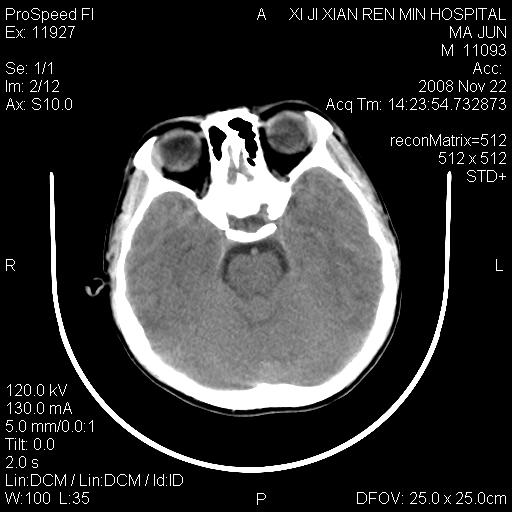

标题: PED1650:男 8岁 间断抽搐2年 两岁是在外院诊断脑瘫 当时CT示 [打印本页]

标题: PED1650:男 8岁 间断抽搐2年 两岁是在外院诊断脑瘫 当时CT示

双侧侧脑室前角,三角区旁及半卵圆中心区白质呈低密度改变,半卵圆中心区病灶呈片状融合趋势,无软化征像,脑室无扩张,各神经核团无异常改变,脑皮质无萎缩等征像,结合病史考虑髓鞘发育不良性脑白质病,异染性脑白质营养不良可能性大.不除外多发性硬化等其他改变,建议磁共振检查

脑白质减少,双侧侧脑室额角旁及半卵圆中心可见对称性略低密度影,边缘尚清,考虑脑白质发育不良